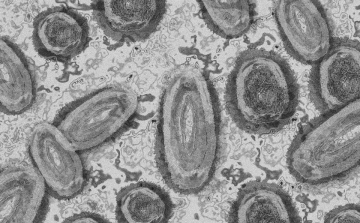

Tovább nőtt a majomhimlő-fertőzöttek száma Magyarországon

Újabb két embernél igazolt majomhimlő-fertőzést a Nemzeti Népegészségügyi Központ (NNK) a 33. héten - augusztus 15-től 21-ig -, ezzel 64-re nőtt a magyarországi esetek száma.

Újabb kilenc, 23-50 éves férfinél igazolták a majomhimlő-fertőzést Magyarországon, ezzel 42-re nőtt a fertőzöttek száma - közölte a Nemzeti Népegészségügyi Központ (NNK) csütörtökön az MTI-vel.

Tovább nőtt a majomhimlő magyar fertőzöttjeinek száma

Újabb hat embernél diagnosztizálták a majomhimlő vírusát, így harmincra emelkedett az igazolt fertőzöttek száma Magyarországon - közölte a Nemzeti Népegészségügyi Központ (NNK) pénteken az MTI-vel.